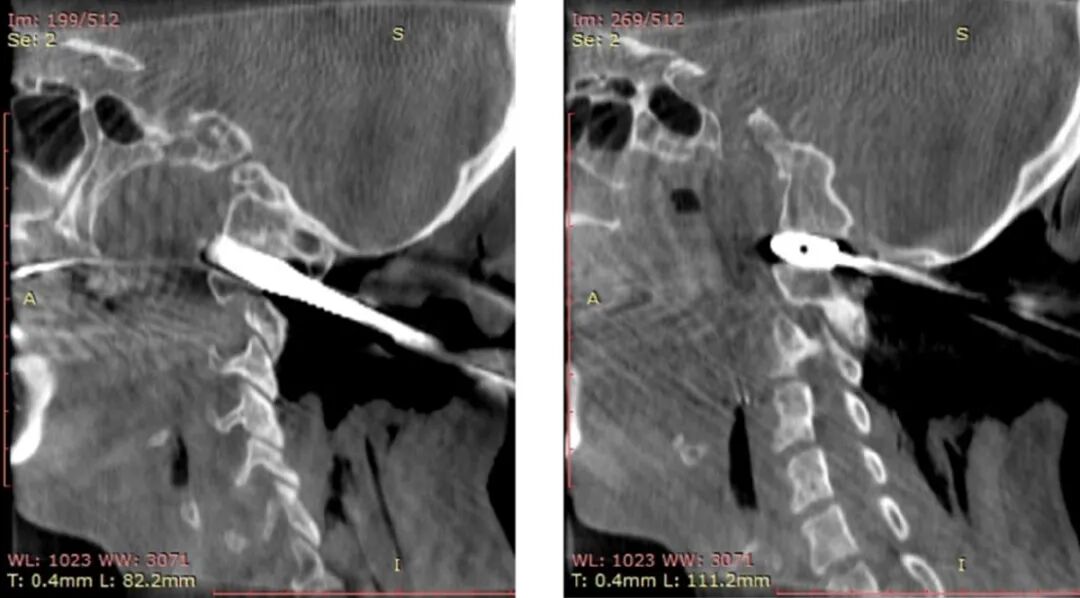

8、术中椎动脉保护

颅颈交界区骨性结构畸形常常伴有椎动脉走行异常,特别是寰枕融合畸形。当寰枕融合畸形发生时,寰椎后弓、两侧侧块、横突与枕骨融合消失,导致椎动脉V3段穿过枢椎横突孔后便失去了寰椎横突孔和寰椎后弓等骨性结构的引导,进而出现走行异常,椎动脉直接向内侧跨过枢椎椎弓峡部进入椎管。椎动脉V3段走行异常会遮挡寰枢椎关节面的后方(图8),增加了从后路在进行寰枢椎关节间操作和寰枢椎椎弓根置钉过程中损伤椎动脉的风险。

此外椎动脉的常见畸形还有椎动脉发育不良、甚至缺如。这导致优势椎动脉损伤后,发生致命性基底动脉缺血的风险增加,因此保护椎动脉是关节间撑开融合技术中的关键环节。

术前常规进行头颈部CTA扫描,应用计算机软件(推荐应用RadiAnt DICOM Viewer, Medixant Co.)对CTA Dicom数据进行三维重建详细观察颅颈交界区骨性结构畸形和椎动脉走行,制定手术方案,评估椎动脉损伤的风险。

根据进行关节间操作时损伤椎动脉的危险程度,将椎动脉走行分为3种类型:低风险型,高风险型,禁忌型低风险型椎动脉:椎动脉走行不遮挡寰枢椎关节面,进行关节间操作损伤椎动脉的风险较低,此类患者通常没有寰枕融合,或寰枕融合不完全,寰椎保留横突孔结构,椎动脉受到寰椎横突孔的引导,走行路径正常,没有遮挡寰枢椎关节面(图9)。

Ⅰ型高风险型椎动脉指患者一侧椎动脉走行异常,手术中损伤几率较高,但对侧椎动脉走行、管径正常,手术中损伤几率较低。手术中高风险椎动脉发生损伤,对侧低风险椎动脉可以代偿基底动脉血运,患者发生后循环缺血的风险较低(图10)。

Ⅱ型高风险型椎动脉,指两侧椎动脉皆为高风险型椎动脉,由于两侧椎动脉均走行异常,因此术中均存在较高损伤风险,如两侧椎动脉同时被损伤,患者可能发生后循环缺血(图11)。

Ⅲ型高风险型椎动脉,指患者一侧椎动脉为高风险性椎动脉,而对侧椎动脉退化或缺如,一旦高风险型椎动脉损伤,对侧椎动脉无法代偿基底动脉血供,可引发致命性基底动脉缺血(图12)

对于高风险型椎动脉,我们采用的治疗策略是将椎动脉向头侧抬起。显露寰枢椎关节后缘后,将关节间撑开器完全插入关节,如此,在旋转撑开器对关节间隙进行撑开的过程中,与椎动脉接触的是撑开器柱状的连接杆,避免对椎动脉造成卡压和切割,降低椎动脉损伤的风险(图13)。

禁忌型椎动脉:椎动脉穿行于寰枢椎关节面,进行寰枢椎关节间操作必然损伤椎动脉(图14)。这种椎动脉走行方式在关节间操作过程中尚无有效办法避开,因此是关节间撑开操作的禁忌证。